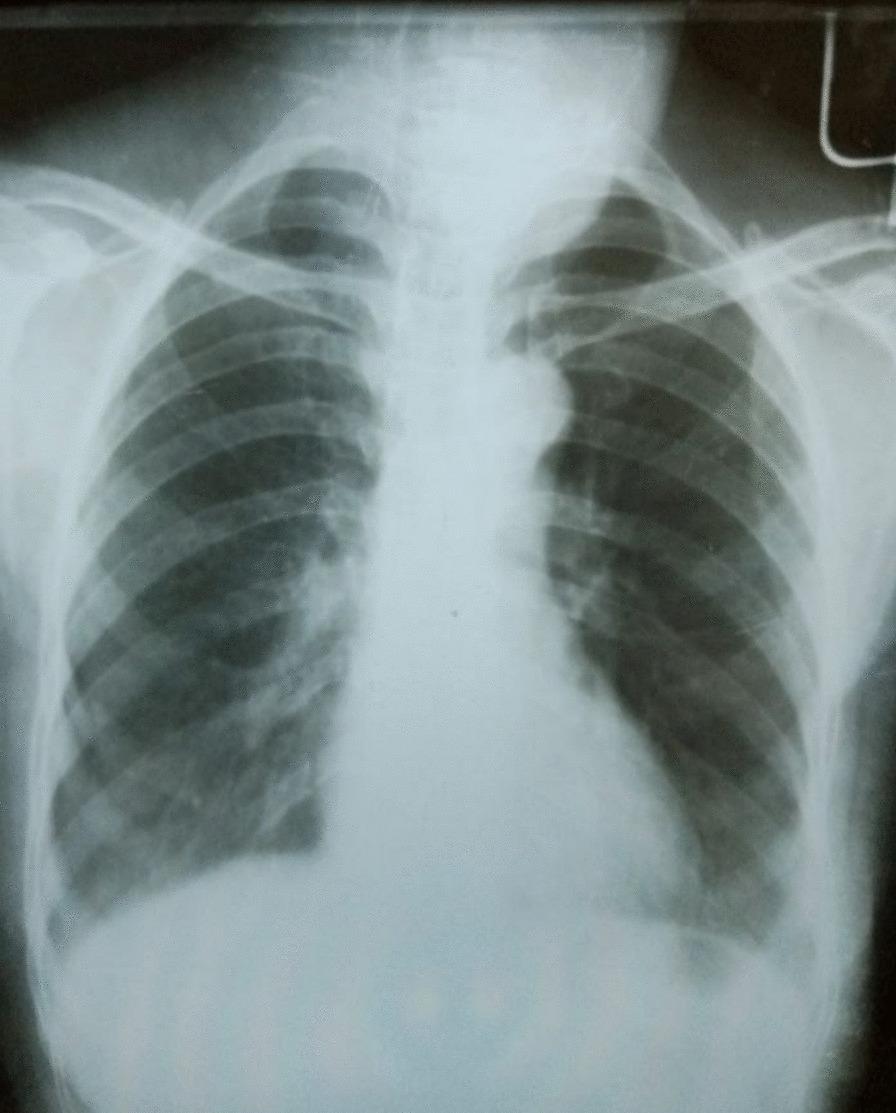

A 60-year-old retired female Ethiopian high-school teacher presented to University of Gondar Hospital, Gondar, Ethiopia with firm, nontender multinodular anterior neck swelling measuring at largest 2 × 3 cm that moves with swallowing. GeneXpert of the pus sample and cytopathology examination confirmed the diagnosis of thyroid tuberculosis, and the patient was started on 2 rifampicin-ethambutol-isoniazid-pyrazinamide/4 rifampicin-isoniazid 3 tablets by mouth/day, which is defined as the preferred first-line anti-tuberculosis regimen in Ethiopia, and pyridoxine 50 mg by mouth per day for 6 months. Since then, she has been followed with regular liver function tests. The patient has shown a smooth course with no significant adverse effects encountered. Currently, the patient has completed her anti-tuberculosis treatment and is doing well.

一名 60 岁的退休埃塞俄比亚女高中教师因触及性、非触痛的颈前多结节性肿胀就诊,最大直径为 2×3cm,可随吞咽移动。脓液样本的 GeneXpert 和细胞病理学检查证实了甲状腺结核的诊断,患者开始接受 2 种利福平-乙胺丁醇-异烟肼-吡嗪酰胺/4 种利福平-异烟肼 3 片口服/天,这是埃塞俄比亚首选的一线抗结核方案,并每天口服 50mg 吡哆醇,持续 6 个月。此后,她定期进行肝功能检查。患者的治疗过程顺利,没有出现明显的不良反应。目前,患者已完成抗结核治疗,情况良好。